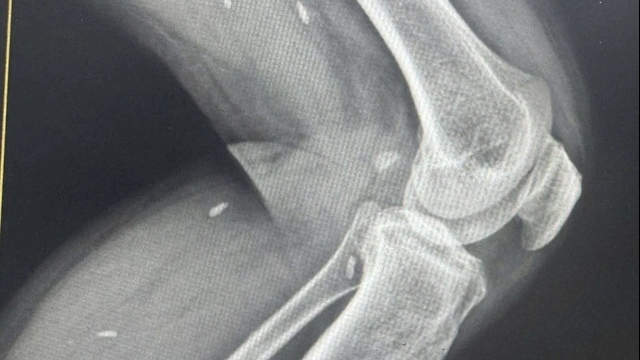

Theo đó, ngày 29/3/2022, do bị đau lưng nên bà H. tới bệnh viện khám và được cho nhập viện vào Khoa Phục hồi chức năng. Sau khi điều trị khoảng 1 tuần bệnh không thuyên giảm, bà H. được chỉ định chụp cộng hưởng từ ngày 5/4.

"Tôi có hỏi bác sĩ Trung về kết quả thì được trả lời tôi bị phồng đĩa đệm và được bác sĩ Trung tư vấn là chữa được bằng cách tiêm thuốc với giá 1,5 triệu đồng/mũi và nói phải tiêm vài mũi mới khỏi. Tuy nhiên, khi y tá phát thuốc, tôi có xem bệnh án thì thấy mình không có bệnh như bác sĩ Trung nói"- bà H. nêu trong đơn.